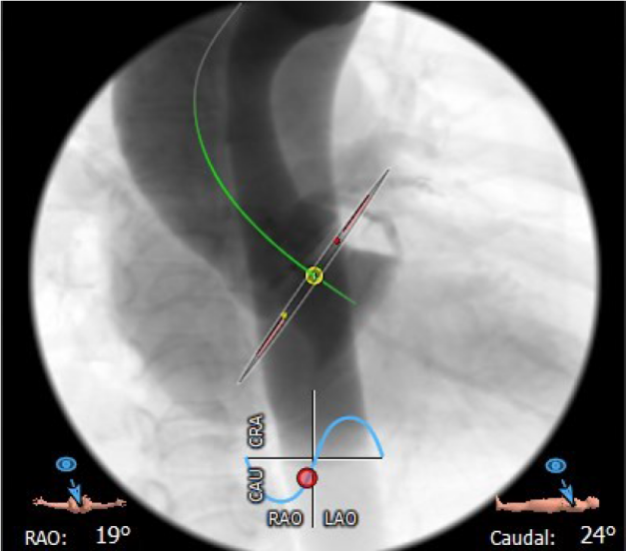

4.患者术中最佳造影角度RAO:19°,CAU:24°。

术中最佳造影角度RAO:19°,CAU:24°